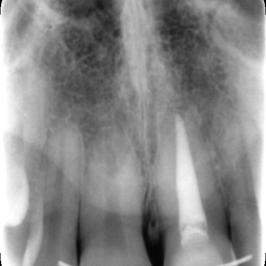

Un ancien traitement de racine est présent sur l'incisive gauche

Il a coloré la base de la dent

Au bout de 2 mois et 4 séances de blanchiment interne